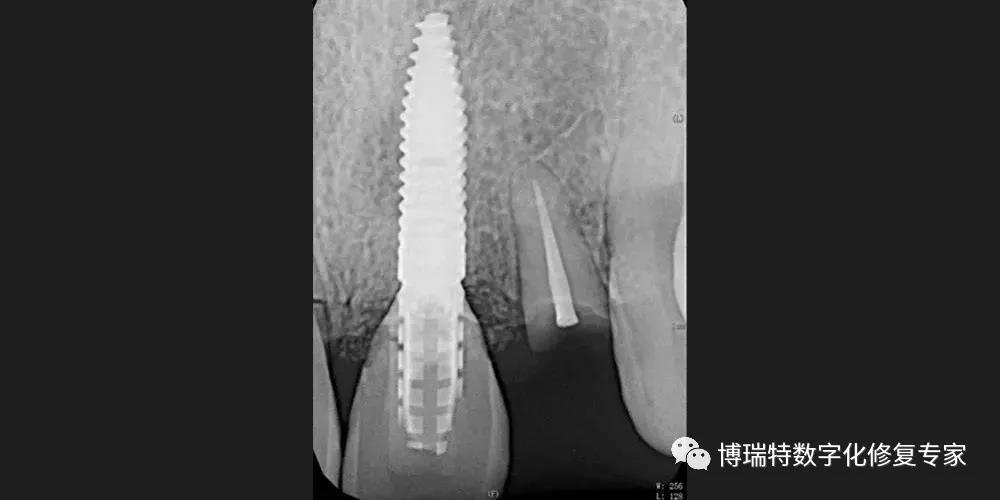

8226; 术后根尖片显示临时基台就位良好;

8226; 术后一周,21牙龈冠向生长;

8226; 术后一月,21残根磨至龈下。

8226; 四个月后,取下临时修复体,见21牙龈高度与11基本一致,穿龈轮廓初步成形,22牙龈基本覆盖断根面;

8226; 取开口式印模,按照理想龈缘位置制作种植体支持式临时树脂单端修复体,口内戴入;

8226; X线示:修复体就位良好。